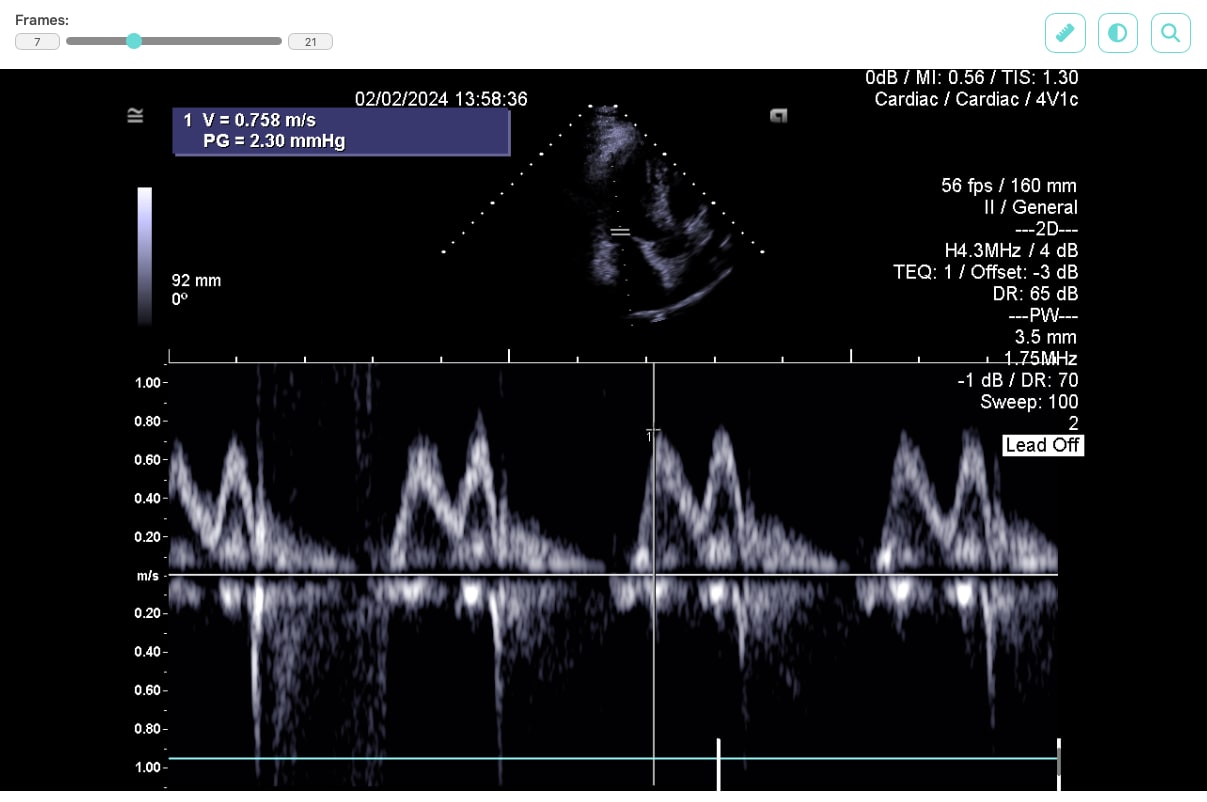

Our task was to design an optimal solution for displaying graphical results of patient examinations, captured using various imaging methods such as X-ray, CT, MRI, or ultrasound, directly within the clinic’s web application. It was necessary to consider both security requirements and the speed of processing large volumes of image data in the specialized DICOM format, which is the standard output format of medical imaging devices and the protocol through which medical devices communicate with each other.

For displaying data on the web, we selected the JavaScript library Cornerstone3D, which not only allows DICOM files to be viewed but also provides features such as adjusting brightness and contrast, or using a ruler to measure distances between displayed parts of the patient’s body.